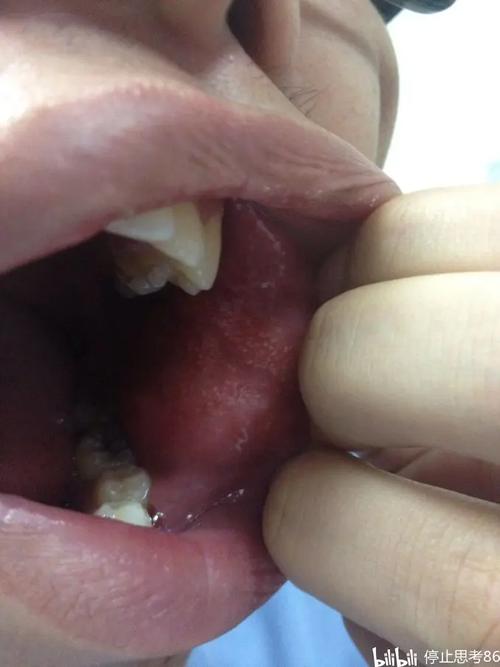

晚期最危险的并发症:癌变

这是OSF晚期最令人担忧的后果。

- 高风险性: 口腔黏膜下纤维化被世界卫生组织列为癌前状态,长期的炎症刺激和细胞代谢异常,使得黏膜上皮细胞发生癌变的几率极高。

- 癌变率: 癌变率报告不一,但普遍认为在 7% - 13% 之间,有些研究甚至更高。

- 特点:

- 不易早期发现: 癌变区域(通常是白色斑块,即“白斑”)与OSF本身的白色病变难以区分,容易被忽视。

- 恶性程度高: 一旦发展为鳞状细胞癌,其侵袭性强,生长迅速,预后较差,治疗难度大。

- 警惕信号:

- 在原有的白色或棕黄色基础上,出现局部红斑、糜烂、溃疡长期不愈。

- 病变区域突然增厚、硬结。

- 自发性出血或轻微刺激后出血。

- 出现不明原因的疼痛或牙齿松动。

- 临床检查: 详细询问病史(特别是槟榔咀嚼史),评估张口度(用手指测量)、检查黏膜颜色、质地、弹性以及有无癌变迹象。

- 活体组织检查: 这是确诊和排除癌变的关键步骤! 医生会从病变最严重的区域取一小块组织进行病理学分析。